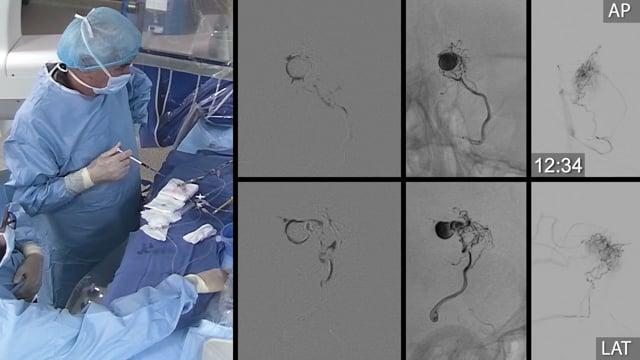

One&Done technique with optiMAX large volume coil

Stent assisted coilingAneurysms